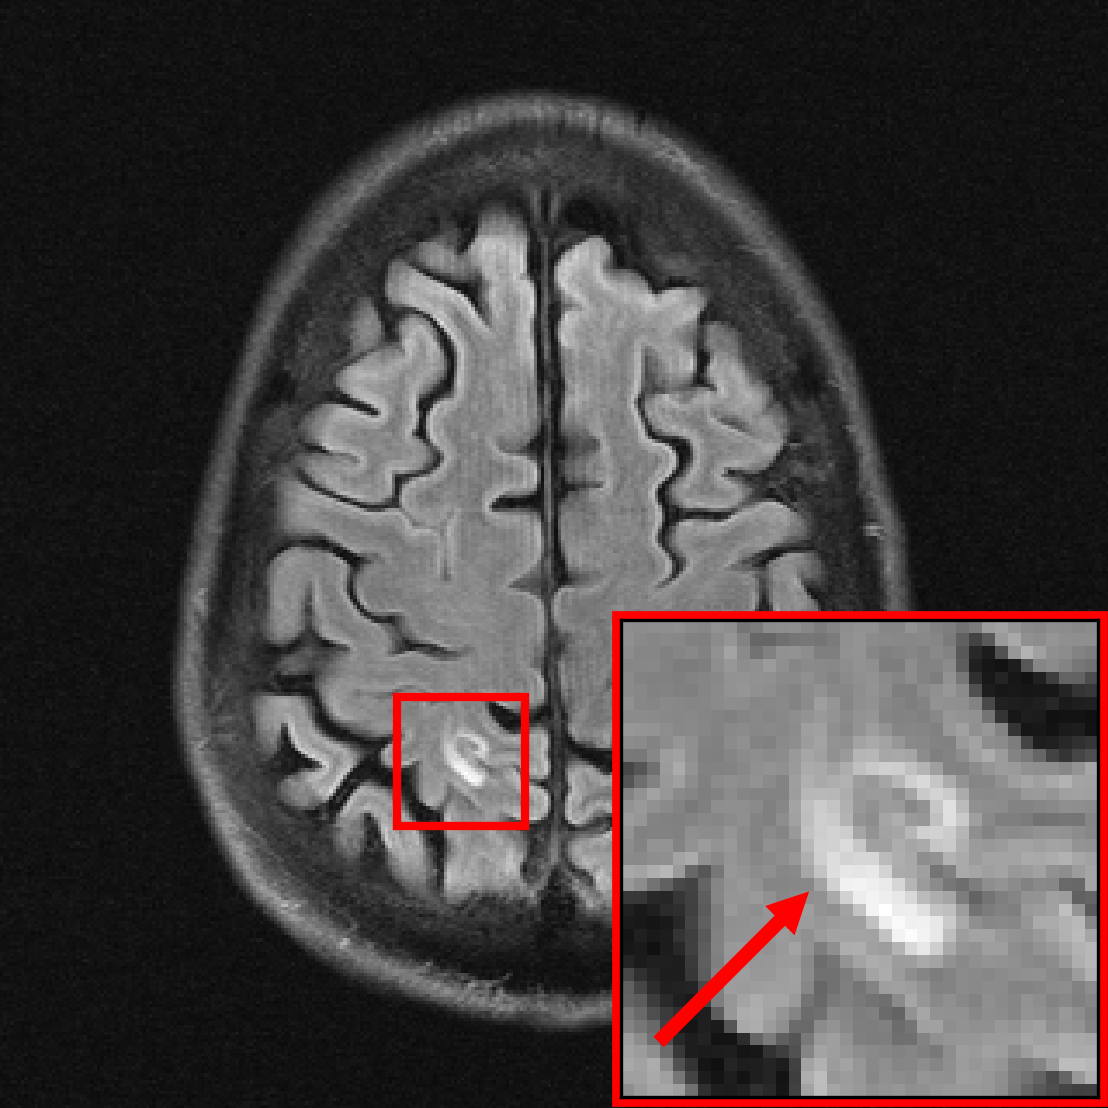

5 Reconstruction of Pathologies Using Data From Healthy Subjects

In this section, we investigate the distribution-shift from healthy to non-healthy subjects by measuring how well models reconstruct images containing a pathology if no pathologies are contained in the training set. We find that models trained on fastMRI data without pathologies reconstruct fastMRI data with pathologies as accurately as the same models trained on fastMRI data with pathologies.

We rely on the fastMRI+ annotations \citepzhaoFastMRIClinicalPathology2022 to partition the fastMRI brain dataset into sets of images with and without pathologies. The annotations cover various pathologies in the fastMRI dataset. We extract a set of volumes without pathologies by selecting all scans with the fastMRI+ label “Normal for age”, and select images with pathologies by taking all images with slice-level annotations of a pathology. The training set contains 4.5k images without pathologies () and 2.5k images with pathologies (). We train U-nets, ViTs, and VarNets on and on , and sample different models by varying the training set size by factors of 2, 4 and 8, and by early stopping. While the training set from distribution does not contain images with pathologies, is a diverse distribution containing data from different scanners and image contrasts.

Figure 7 shows the models’ performance on relative to their performance on . Reconstructions are evaluated only on the region containing the pathology, where we distinguish between small pathologies ( of the total image size) and large pathologies ( of the total image size) to see potential dependencies on the size of the pathology.

We see that the models trained on show essentially the same performance (SSIM) as models trained on regardless of pathology size. The results indicate that models trained on images without pathologies can reconstruct pathologies as accurately as models trained on images with pathologies. This is further illustrated in Figure 8, where we show reconstructions given by the VarNet of images with a pathology: The model recovers the pathology well even though no pathologies are in the training set. We provide additional results, reconstruction examples, and discussion in Appendix E, including a more nuanced evaluation of the SSIM values for VarNet (Figure 16).